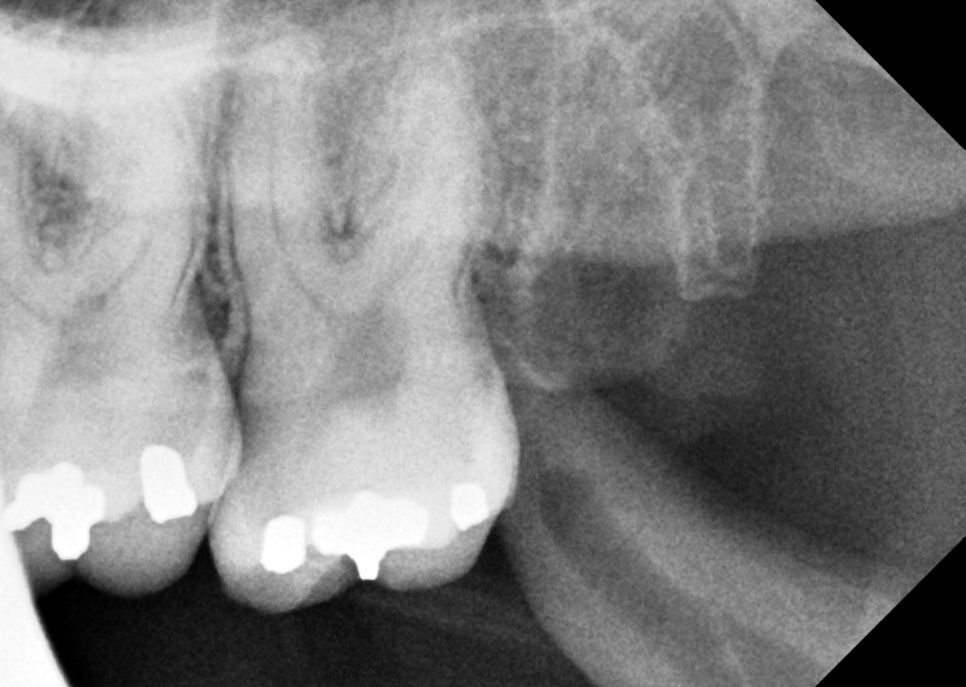

엑스레이를 보고 바로 느낀 건 ‘쉽지 않다’였어요.

잇몸 속에 묻혀 있는 형태는 육안으로 확인하기가 힘들어서 엑스레이를 통해 정확한 상태를 확인해 봤는데요.

촬영일 : 251121

위쪽은 똑바로 나있었지만 아래 사랑니가 모두 매복 되었고 뿌리가 두 갈래로 갈라져 있었으며, 끝이 많이 휘어 있는 형태였어요.

또, 뿌리 끝과 하치조신경관의 거리가 매우 가까웠는데요.

이런 경우, 발치하다가 하치조신경관이 손상되는 경우도 있어서 매우 조심해야 됩니다.